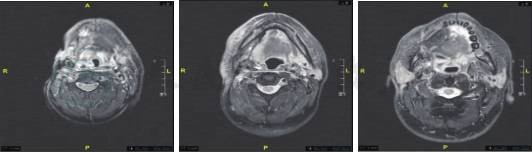

图2 右舌癌术后复发,右咽后、左侧颈上淋巴结转移可能,较前明显缩小

术区部分正常组织缺损,可见皮瓣修复,皮瓣后缘及下方、右颌下、颈鞘区、右侧口咽壁见软组织增厚,边界不清,呈T1WI等、T2WI压脂高信号,增强后环形强化,邻近舌骨骨质破坏,增强后可见不均匀强化,右咽后、左侧颈上见环形强化淋巴结影,大者直径12mm,右咽后淋巴结较前(2018-12-11CT)明显缩小